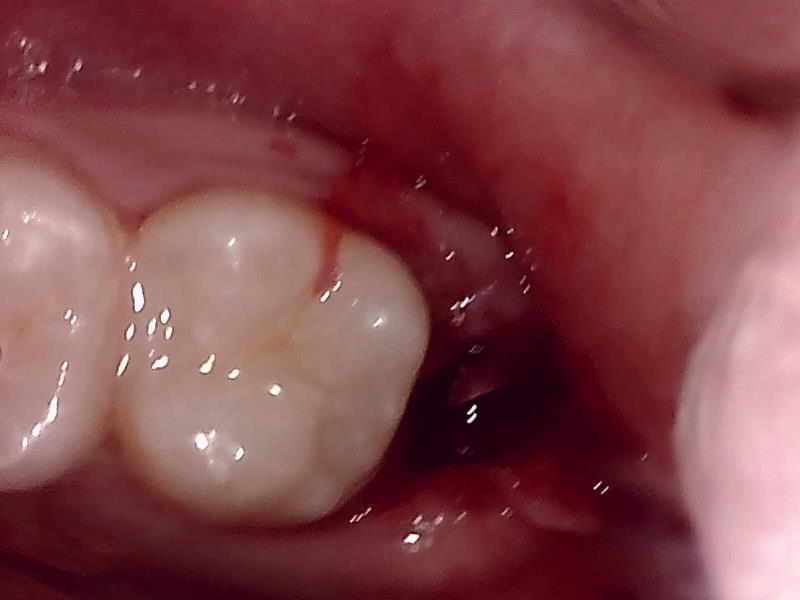

左下の抜歯窩

左下の縫合

治癒

抜歯後、経過良好です。